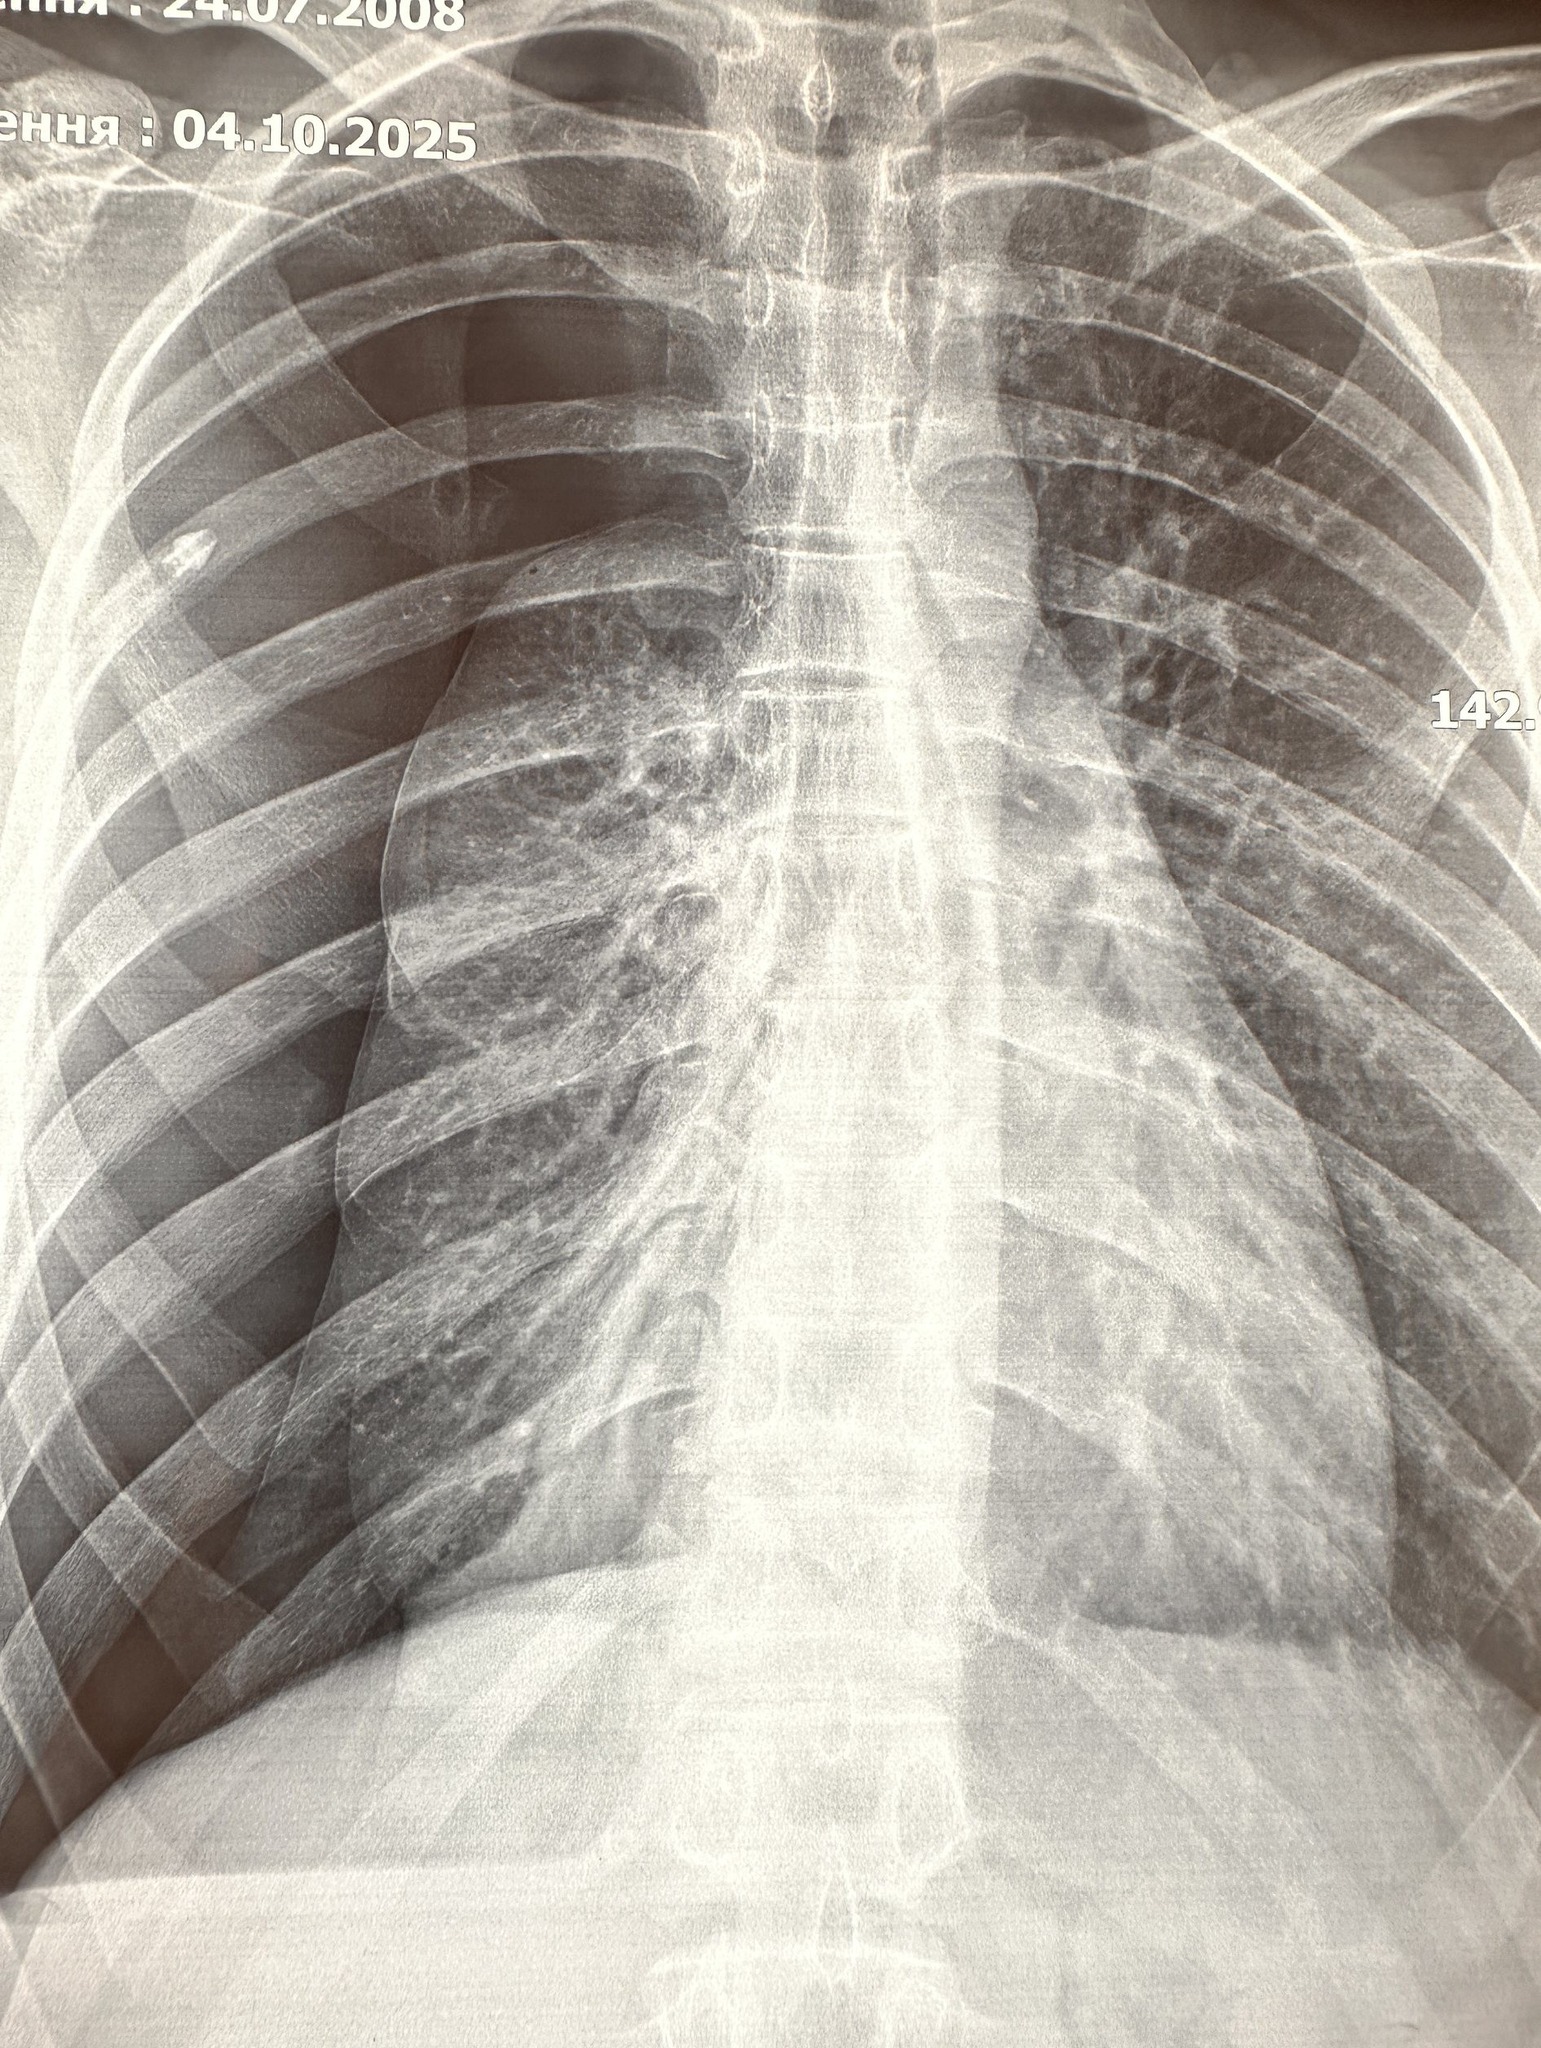

“При обстеженні встановлено попередній діагноз – спонтанний пневмоторакс справа. Проведено дренування плевральної порожнини, але в динаміці ефекту в лікуванні не було. При дообстеженні встановлено діагноз – бульозна хвороба правої легені, правобічний пневмоторакс. Після цього вперше в ОДКЛ проведено малоінвазивну операцію – торакоскопічну резекцію ураженого сегменту правої легені”, – йдеться у повідомленні.